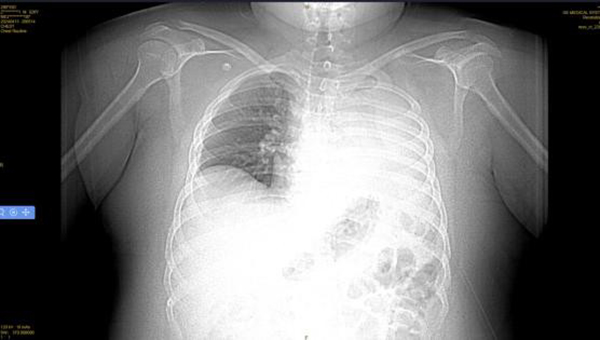

4月14日,王先生因“憋喘伴發(fā)熱咳嗽半月余”到徐州醫(yī)科大學附屬醫(yī)院急診就診。據(jù)王先生家人介紹,患者半個多月來,憋喘不斷加重,先后在徐州市多家醫(yī)院就診,考慮左肺不張伴感染,但通過積極抗感染治療,憋喘無改善并逐漸加重,同時出現(xiàn)發(fā)熱癥狀,體溫最高近39攝氏度。徐醫(yī)附院呼吸與危重癥醫(yī)學科何軍主任會診后,考慮患者智力異常,進食方式特殊,不排除誤吸的情況,閱片后發(fā)現(xiàn)左主支氣管內(nèi)存在異物可能,需行氣管鏡檢查進一步明確肺內(nèi)情況?紤]患者一般情況差,存在I型呼吸衰竭,肺部感染重等情況,于是將其收治在呼吸重癥監(jiān)護室(RICU)。

患者入院后進行高流量氧療和抗感染治療,因為其肥胖合并呼吸衰竭,肺部感染重,氣管鏡風險高,在與家屬充分溝通后,呼吸ICU團隊于4月15日為王先生行床旁氣管鏡檢查,鏡下發(fā)現(xiàn)左主支氣管內(nèi)一白色圓形異物,表面為壞死覆蓋,清除壞死組織后,異物質(zhì)硬,表面光滑,無法鉗取。同時患者病情危重、麻醉評估風險極高,在陳碧主任的主持下,呼吸ICU團隊經(jīng)過討論后決定行床旁氣管鏡取異物術。

季磊副主任醫(yī)師在楊翌、蔣宇及劉慧醫(yī)師的協(xié)助下,在全麻下經(jīng)氣管插管(8#)套管進鏡,左主支氣管內(nèi)可見被粘痰、壞死物包裹一圓形異物,清理后發(fā)現(xiàn)異物為花生粒,長徑約2cm,由于花生粒過大,無法通過8#氣管導管,于是將花生粒分解,通過使用圈套器、異物鉗以及網(wǎng)籃逐一將其取出,總共歷時1.5個小時。取出異物后,左主支氣管及其分支可見大量黃色膿性分泌物,予以充分吸除。

后續(xù)給與積極抗感染等治療,復查胸片示左肺不張改善,體溫正常,炎癥指標下降,再次復查氣管鏡下可見痰量較前明顯減少,總體病情好轉,4月23日轉到普通病房繼續(xù)治療;颊呒覍俦硎,輾轉三家醫(yī)院就醫(yī),還是徐醫(yī)附院最值得信任,對呼吸ICU全體醫(yī)護人員表達了敬意和衷心感謝。